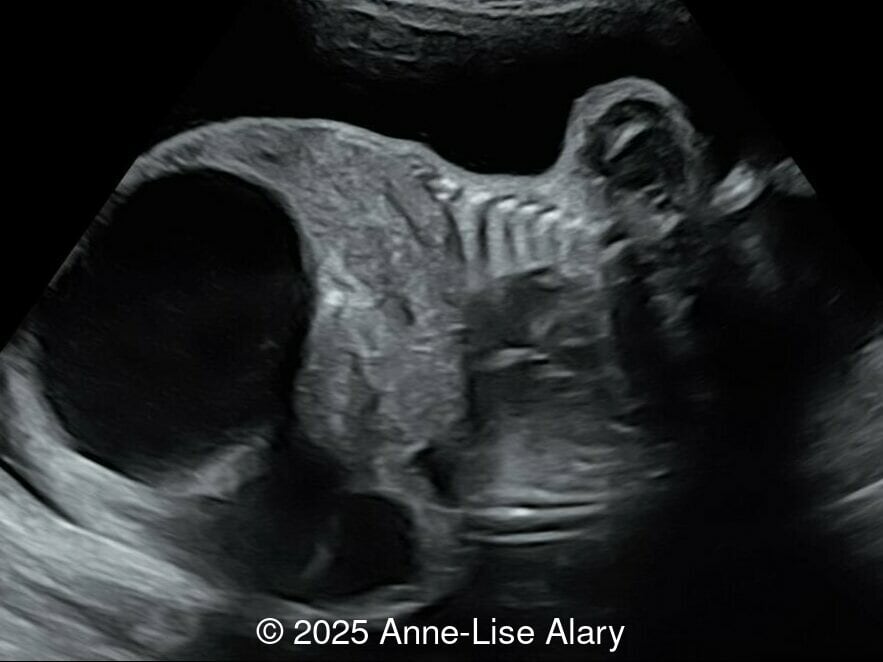

Axial image of the abdomen

Image 3 Axial image of the abdomen

Our prenatal ultrasound revealed a male fetus with megabladder, dilation of both ureter and kidneys, and thinned kidney parenchyma consistent with Lower Urinary Tract Obstruction (LUTO).  Additional findings suspected on ultrasound and confirmed on computed tomography included:

• Suspicion of dilated bowel in the left flank, in addition to dilated urinary tract

The diagnosis of PBS is often made in the second trimester of pregnancy, although it has been described as early as 11 weeks of gestation [20]. The most frequent ultrasound findings are a large, thin-walled bladder accompanied by bilateral hydroureter/hydronephrosis, dysplastic kidneys with echogenic renal parenchyma and renal cortical cysts, and abdominal wall laxity which is better viewed after bladder decompression [21]. Cryptorchidism can be detected prenatally by 28 to 30 weeks gestation when the testes descend into scrotum. There may be a patent urachus, visible as a cystic connection between bladder and umbilicus. Oligohydramnios is a frequent finding, which makes it difficult to visualize the associated anomalies.